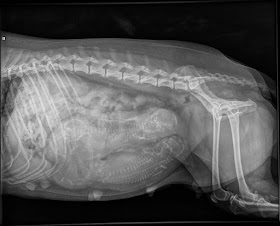

Käytiin kurkkaamassa Novan mahaan vielä röntgenissäkin, samalla haettiin toinn herpes-rokote.

Eläinlääkäri laski kalloja kolme, mutta toisaalta arvottiin neljännenkin mahdollisuutta. Viikon päästä ollaan todennäköisesti viisaampia, kun ollaan pupsit saatu maailmaan <3.